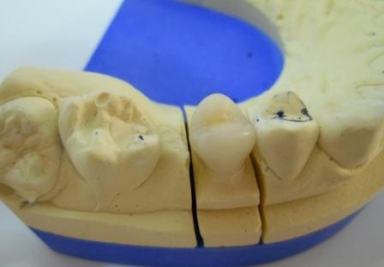

Full ceramic crown on central incisor

full ceramic crown on central incisor, professional cleaning